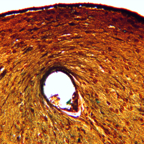

Brain - 145-426 25x large cut OT.jpg

Brain - 224-2 60x testx.jpg

Brain - 224intact caudate putMEN 224-224 60X.jpg

Brain - 244 caudate low power 2x.jpg

Brain - 244 healed caudate putamen.jp2

Brain - 244 healed caudate putamen.jpg

Brain - 244 intact caudate putamen.jpg

Brain - 409-333 MH detour.jpg

Brain - 59-1123 4x large 18d fimbria massive detour.jpg

Brain - 59-422 remodeling of optic tract.jpg

Brain - 59-422, 10x16x.jpg

Brain - 59-422,12x40l remodeling of optic tract detail.jpg

Brain - 77-214 SM 100 oilcon not lzw.jpg

Brain - 77-214 SM 4x large hiest LUTScrop8.jpg

Brain - 77-214 sm z 40xopa 1t08 undulating neurons.jpg